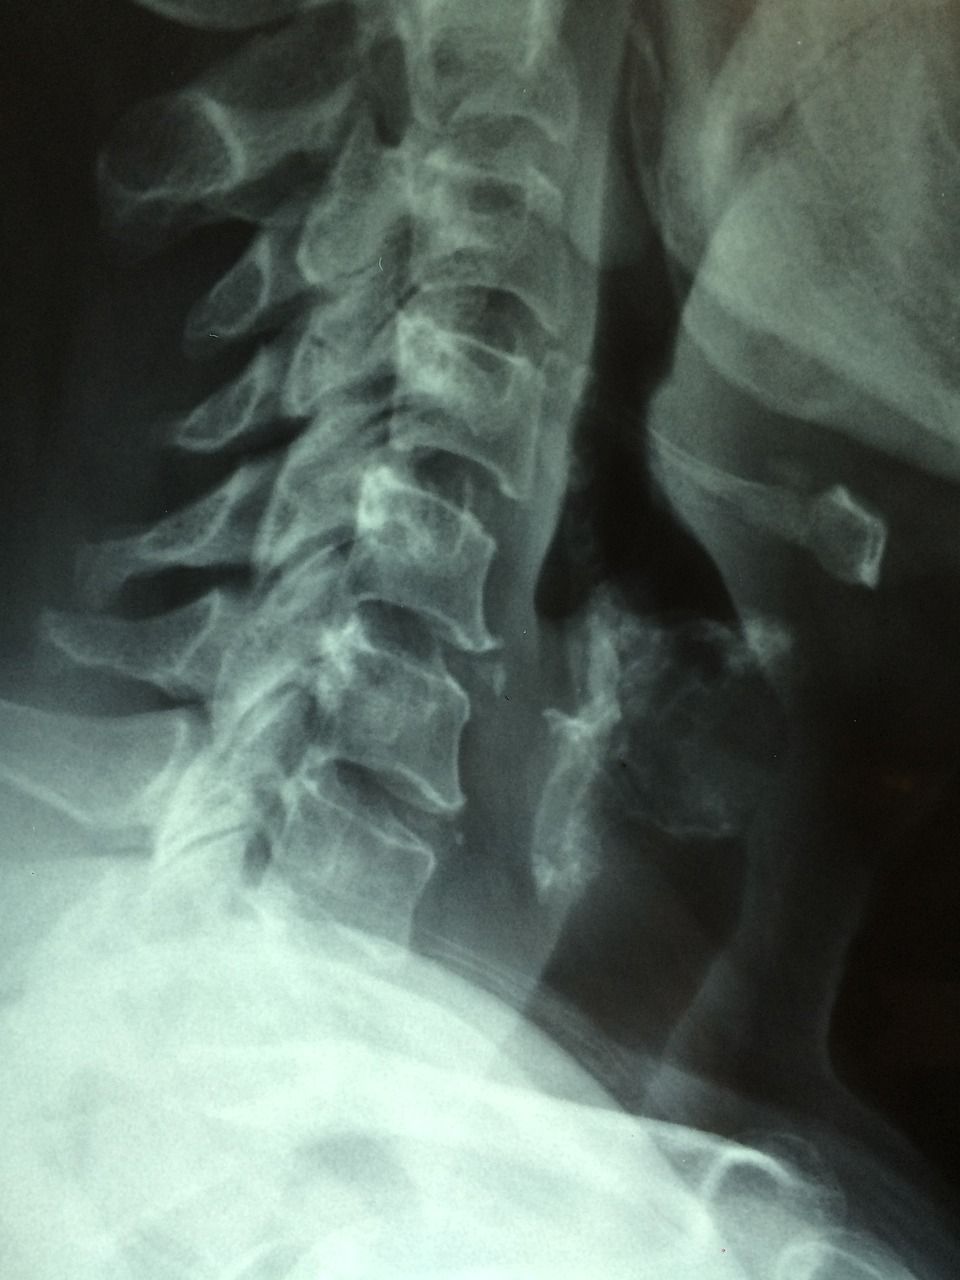

Røntgenundersøgelse